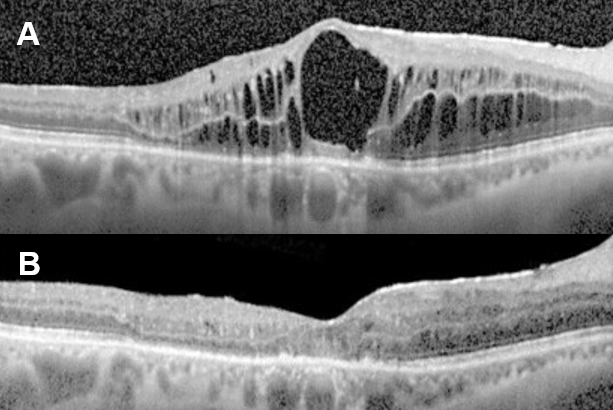

- 레이저 유리체 융해술(Nd:YAG Vitreolysis) – 네오디뮴 야그레이저를 이용하여 절개창에 낀 유리체를 풀어주는 시술입니다(그림 5).

그림 5. (A)절개창에 끼워져 있는 유리체(Vitreous incarceration, Vitreous winksyndrome), (B)야그레이저 광원에 끼워져 있는 절개창을 조준하였으며, (C)야그레이저 조사 후 절개창에 끼워져 있던 유리체는 풀렸습니다.2) 유리체절제술(그림6) ① 절개창(창상) 내 또는 홍채와의 유착된 유리체 제거 ② 기존 유리체 제거 → 염증매개물질이 포함되어 있던 유리체를 제거함으로써 염증반응 감소 + 눈 깊은 내부로 약물 침투를 좋게 할 수 있습니다.③ 수술은 CME가 2개월 이상 지속됐을 때 시도해 볼 수 있지만 수술 자체가 가진 위험성과 수술 후에도 시력 호전이 없을 수도 있다는 사실을 반드시 환자에게 충분히 설명해야 합니다.

그림6.(A) 수술 전 전형적인 CME의 FAG 누출을 확인할 수 있으며, (B)유리체절제술 1개월 후 실시한 FAG에서 꽃 모양누출과 시신경 부위의 누설이 확실히 줄어든 것을 알 수 있습니다.3) CME를 일으키는 인공수정체를 제거하고 다른 것으로 대체하는 방법도 있습니다.남들이 하는 백내장 수술, 하면 다들 세상이 밝아진다고 들었는데 왜 나는 잘 보이지 않을까.어떤 수술이든 부작용과 합병증은 있어요. 100% 안전한 수술이 있다면 그 질환은 수술로 해결할 수 있기 때문에 더 이상의 연구도 필요 없을 것입니다.보다 안전한 수술, 수술을 받는 사람과 하는 사람 모두에게 부담을 덜 수 있는 방향을 찾기 위해 사람들은 계속 연구하고 발전해 나갈 것입니다.그러기 위해서는 지금의 문제, 현황을 잘 알고 있는 것이 중요하다고 생각합니다. 그래서 오늘도 어려운 눈이야기를 함께 공부해 보았습니다.수고하셨습니다!